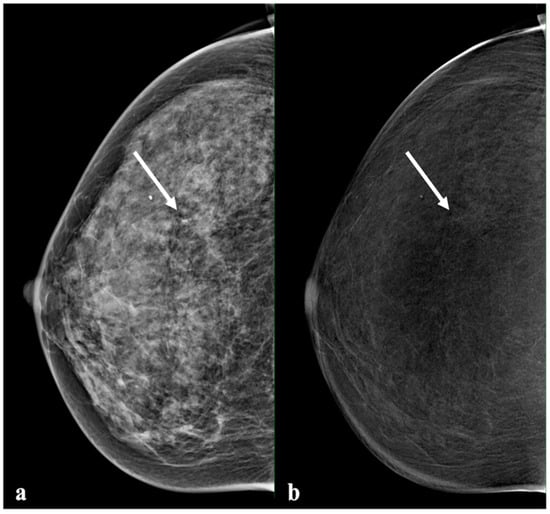

2.2. Contrast-Enhanced Mammography

2.3. Image Analysis